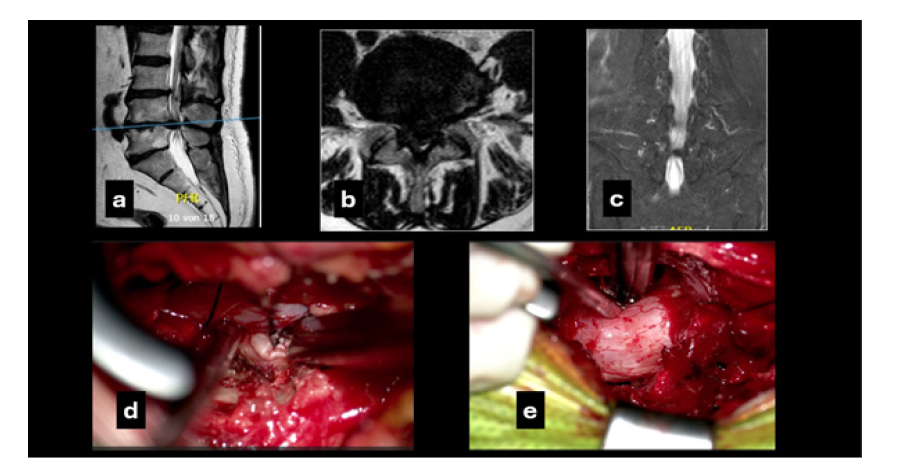

A 65-year-old obese male (BMI 31.3) presented emergently with severe immobilizing low back pain (VAS 8) and bilateral sciatica, more pronounced on the right (VAS 9). He reported months of right lumbosacral radiculopathy and recent bowel and bladder dysfunction. Neurological examination revealed right foot dorsiflexion weakness (2/5), right L5-S1 hypoesthesia and decreased perineal sensation. MRI demonstrated a massive L4-L5 disc herniation with subtotal canal obstruction, classified as type 3A (AFFM-YOLOv8). Postoperatively, bowel and bladder function improved and neurological deficits regressed significantly. At follow-up, complete neurological recovery and progressive weight reduction were documented. Post-rehabilitation ODI was 41. VAS improved to 3 for back pain and 2 for leg pain (Figure 3).

Figure 3:The preoperative T2W magnetic resonance imaging mid sagittal (a) and axial (b) views showing the massive disc herniation and the osteophyte growth that accompanies disc extrusion at the level L4-L5; (c) coronal T2-weighted MRI of the lumbosacral spine. The bright vertical column in the midline represents Cerebro Spinal Fluid (CSF) within the thecal sac. The CSF column appears constricted at the L4-L5 level, with a focal indentation consistent with severe central canal stenosis produced by the large disc herniation combined with the degenerative changes. Intraoperative photomicrographs: (d) it shows how the herniated disc is being removed ipsilaterally with a disc forceps and the help of the aspirator tip, which is slightly retracting the dural sac; (e) after tilting the table about 25 degrees and having partially removed the material from the contralateral disc, the osteophytes are removed with a Kerrison punch, while the nerve and dural structures are held slightly apart with the tip of the aspirator.